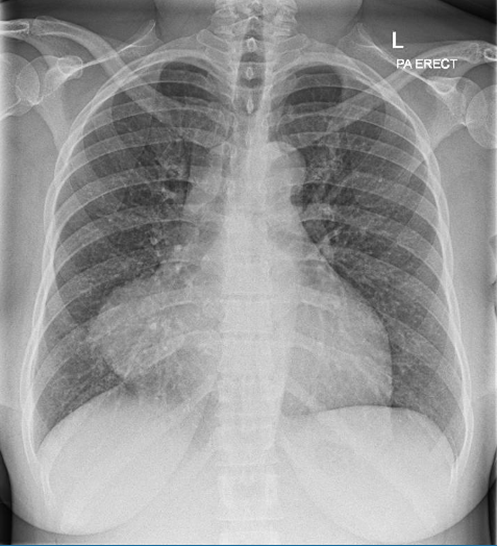

CXR was performed on admission which is shown below:

CXR was performed on admission which is shown below